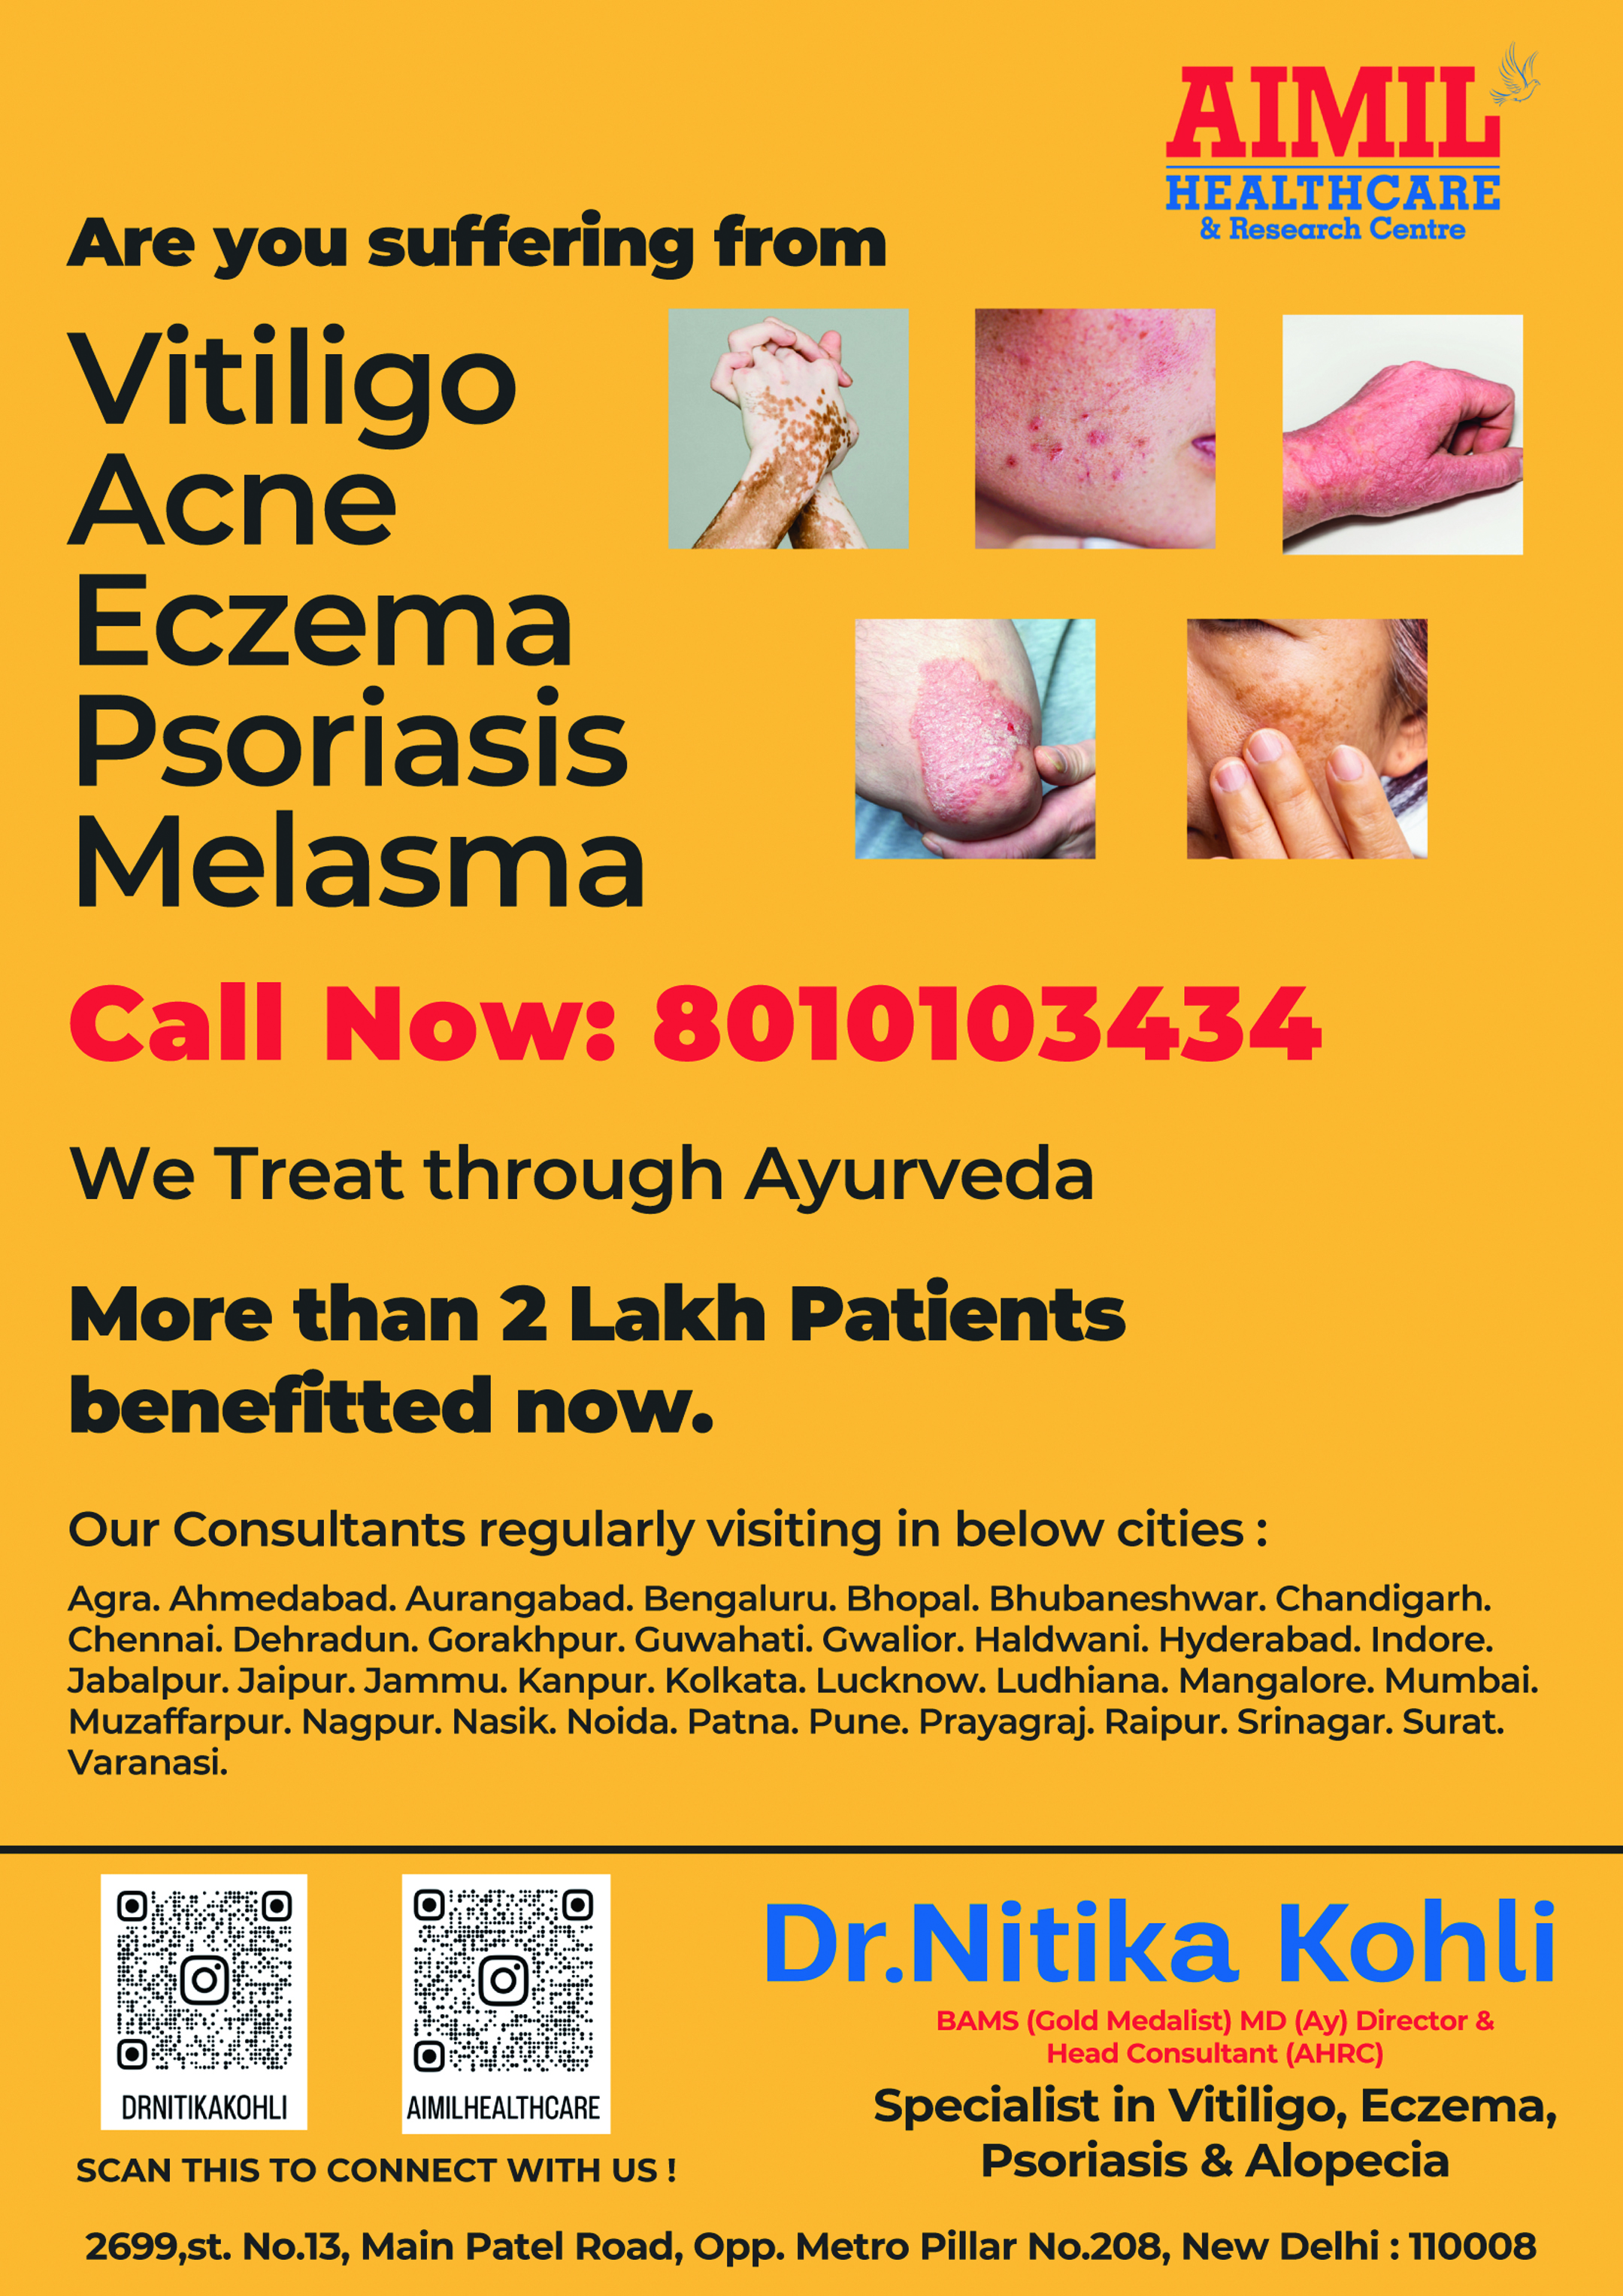

Company name: Aimil Healthcare

Contact No: 8010103434

Contact Person Name: Sales